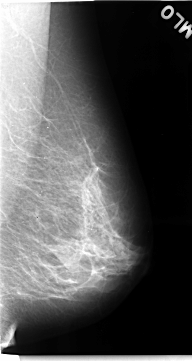

C_0068_1.RIGHT_MLO

RIGHT_MLO LINES 4624 PIXELS_PER_LINE 2592 BITS_PER_PIXEL 12 RESOLUTION 50 OVERLAY